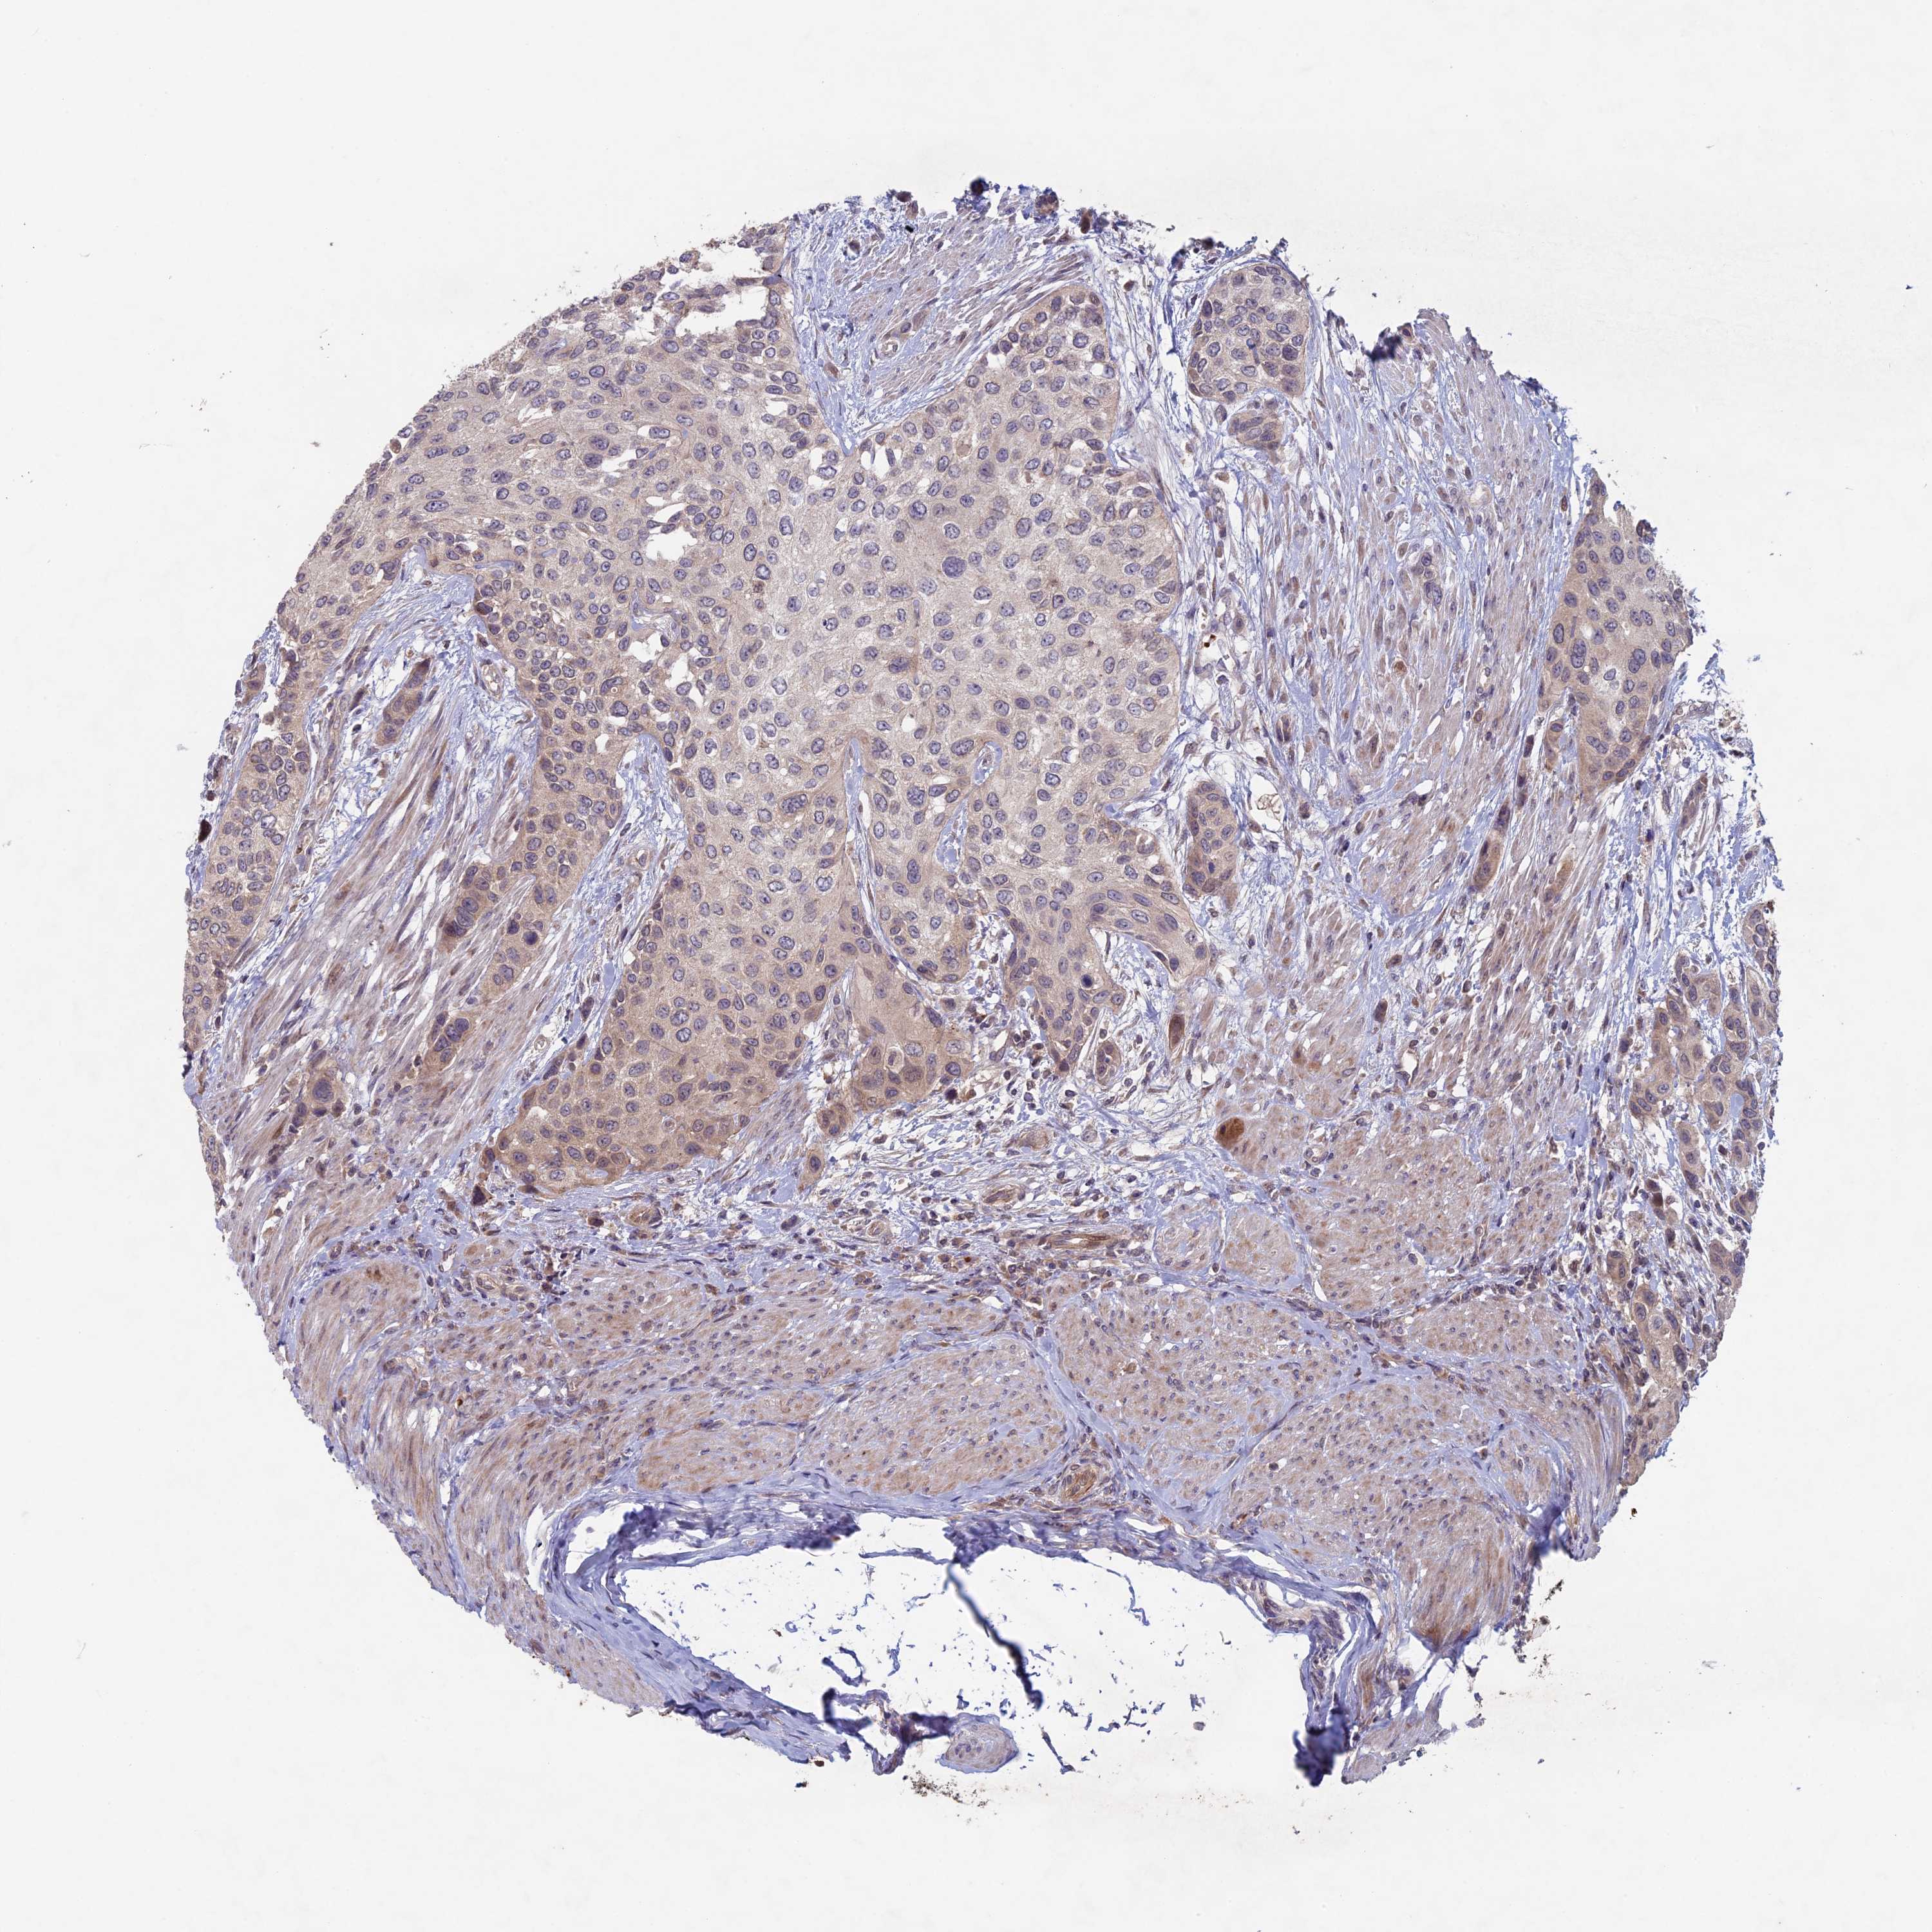

UROTHELIAL CANCER - Protein expressioni

A mouse-over function shows sample information and annotation data. Click on an image to view it in a full screen mode. Samples can be filtered based on level of antibody staining by selecting one or several of the following categories: high, medium, low and not detected. The assay and annotation is described here.

Note that samples used for immunohistochemistry by the Human Protein Atlas do not correspond to samples in the TCGA dataset.

Antibody stainingi

Antibody staining in the annotated cell types in the current human tissue is reported as not detected, low, medium, or high, based on conventional immunohistochemistry profiling in selected tissues. This score is based on the combination of the staining intensity and fraction of stained cells.

Each image is clickable and will lead to virtual microscopy that enables deeper exploration of all samples and also displays staining intensity scores, fraction scores and subcellular localization as well as patient and tissue information for each sample.

Antibody HPA039683

Antibody HPA040776

Staining

High

Medium

Low

Not detected

Intensity

Strong

Moderate

Weak

Negative

Quantity

>75%

75%-25%

<25%

None

Location

Nuclear

Cytoplasmic/membranous

Cytoplasmic/membranous,nuclear

Urothelial carcinoma, High grade